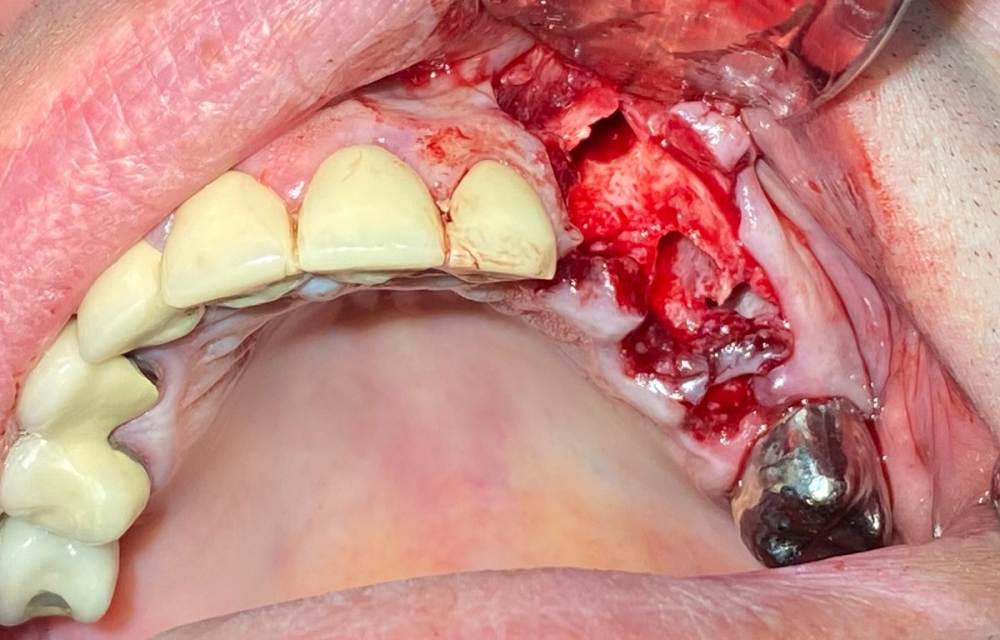

Женька Опубликовано 18 апреля, 2021 Автор Поделиться Опубликовано 18 апреля, 2021 (изменено) Наконец-то я прооперировал нашего барабанщика. До этого, изготовили каппу с гарнитурными зубами, спс коллеги за советы! Каппу наш пациент благополучно сломал, хотя как говорит приём пищи был без неё... В итоге сделал ему шаблон под пилот, новую каппу и... ни b2s ни idr, а что-то другое...) В общем удалил 3 зуба, поставил 2 имплантата, с нёба сдт с деэпителизацией, край лунки 2.4 отстучали и уложили в области дефекта 2.3 зуба, пытался как-то заклинить кусочки кости, но так особо и не получил стабильности высокой...фоток с заглублением имплантатов не сделал, спешил, всё заняло у меня целых 4 часа (не знаю где я копался, может потому что периодически делали перерывы на "отдых") Завтра сделаю фото как всё заживает (2 сутки) Очень переживаю, что всё развалится (пациент любит принять на грудь, рок-н-рольщик же и плюсом много курит) удалял кстати говоря дедовским способом, линдеман от комет и поехали. Клык, на удивление, ушел быстрее всех остальных, одно движение люксатором нёбно и он уже весь подвижный. Изменено 18 апреля, 2021 пользователем Женька Добавил фото Ссылка на комментарий

Женька Опубликовано 19 апреля, 2021 Автор Поделиться Опубликовано 19 апреля, 2021 Вторые сутки. Прокуренная губка это фи конечно... Ссылка на комментарий

Женька Опубликовано 23 апреля, 2021 Автор Поделиться Опубликовано 23 апреля, 2021 И вишенка на торте на 4 сутки губка вывалилась думаю она послужила причиной инфекции ну и криворуки конечно... молюсь, чтобы имплантаты остались живы вот тебе и idr *хнык* Ссылка на комментарий

Карен Аванесов Опубликовано 29 апреля, 2021 Поделиться Опубликовано 29 апреля, 2021 23.04.2021 в 17:48, Женька сказал: И вишенка на торте на 4 сутки губка вывалилась думаю она послужила причиной инфекции ну и криворуки конечно... молюсь, чтобы имплантаты остались живы вот тебе и idr *хнык* Кстати, тонкие ниточки, на фоточке красиво, но слабовато ранку держат, вот губка и выпала. Ссылка на комментарий

Женька Опубликовано 29 апреля, 2021 Автор Поделиться Опубликовано 29 апреля, 2021 8 часов назад, Карен Аванесов сказал: Кстати, тонкие ниточки, на фоточке красиво, но слабовато ранку держат, вот губка и выпала. В любом случае это не повод шить четвёркой. А повод задуматься, что надо было плотнее ушить Ссылка на комментарий